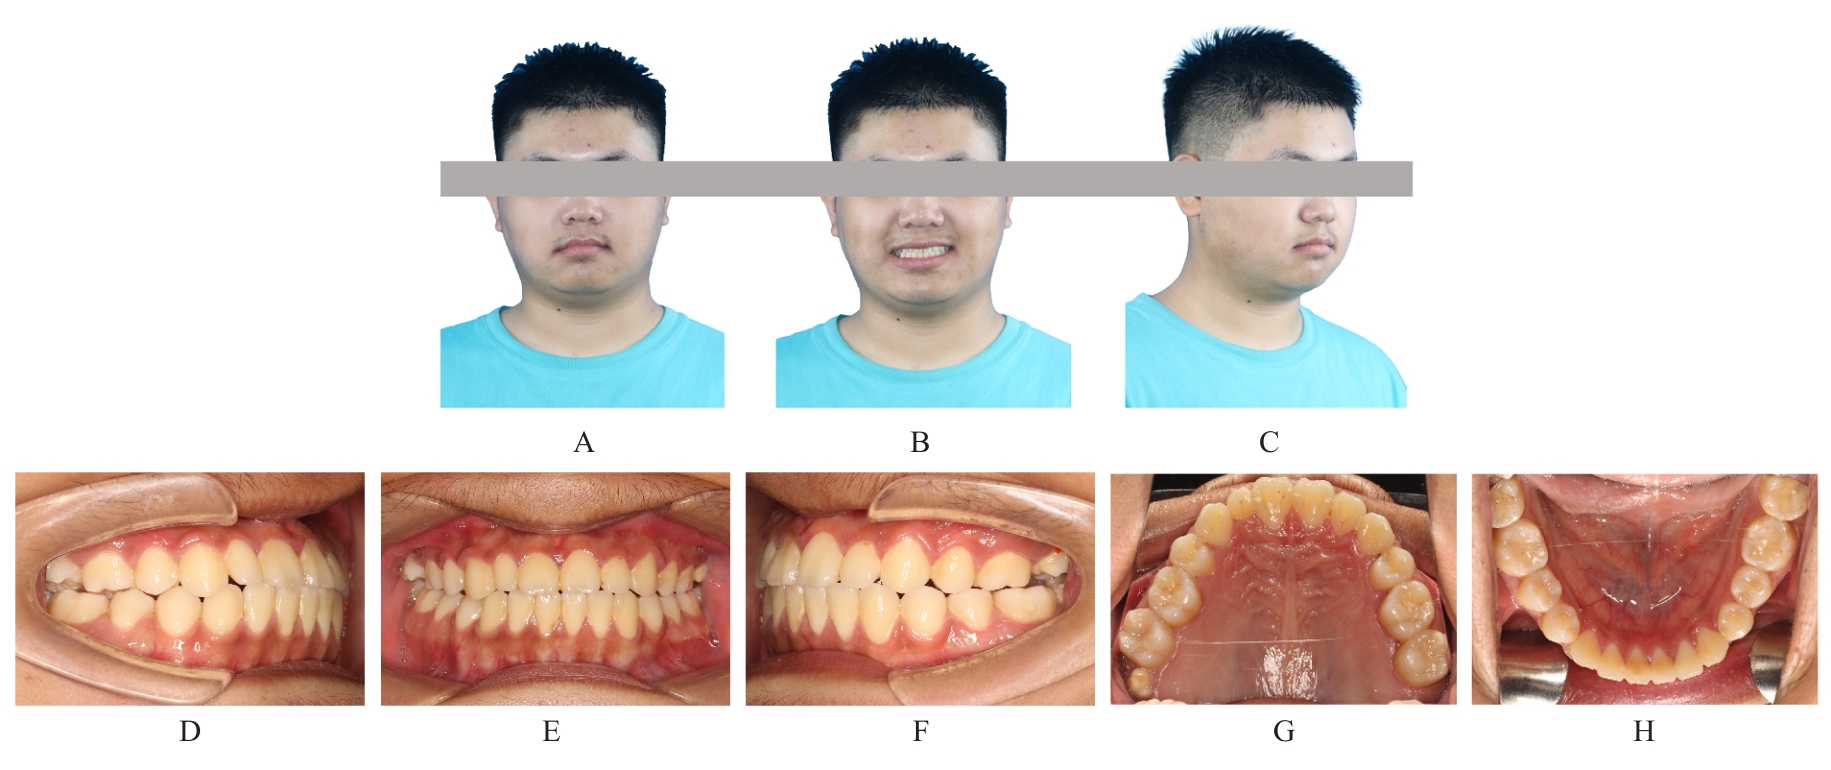

Grade Ⅲ open bite complicated with tongue hypertrophy treated by mandibular incisor extraction:A case report and literature review

Tab.1

Cephalometric detection analysis of patient with grade Ⅲ open bite complicated with tongue hypertrophy before and after treatment"

| Measurement | Normal (x±s) | Pretreatment | Posttreatment |

|---|---|---|---|

| SNA (°) | 82.8±4.0 | 84.1 | 83.8 |

| SNB (°) | 80.1±3.9 | 80.7 | 82.2 |

| ANB (°) | 2.7±2.0 | 3.4 | 1.6 |

| MP-SN (°) | 32.5±5.2 | 35.2 | 32.4 |

| U1-SN (°) | 105.7±6.3 | 116.9 | 111.8 |

| U1-NA (mm) | 5.1±2.4 | 6.7 | 6.6 |

| U1-NA (°) | 22.8±5.7 | 32.8 | 28.1 |

| L1-MP(°) | 92.6±7.0 | 105.7 | 93.4 |

| L1-NB (mm) | 6.7±2.1 | 8.7 | 6.8 |

| L1-NB (°) | 30.3±5.8 | 41.6 | 28.0 |

| U1-L1 (°) | 125.4±7.9 | 102.1 | 122.4 |

| Wits (mm) | -1.1±2.0 | -2.4 | -2.0 |

| APDI (°) | 86.0±4.0 | 80.8 | 85.5 |

| ODI (°) | 73.3±5.9 | 66.0 | 68.0 |

| S-Go (mm) | 80.0±4.0 | 79.7 | 82.1 |

| N-Me (mm) | 112.0±7.0 | 118.9 | 119.5 |

| S-Go/N-Me (%) | 63.0±2.0 | 67.0 | 68.7 |